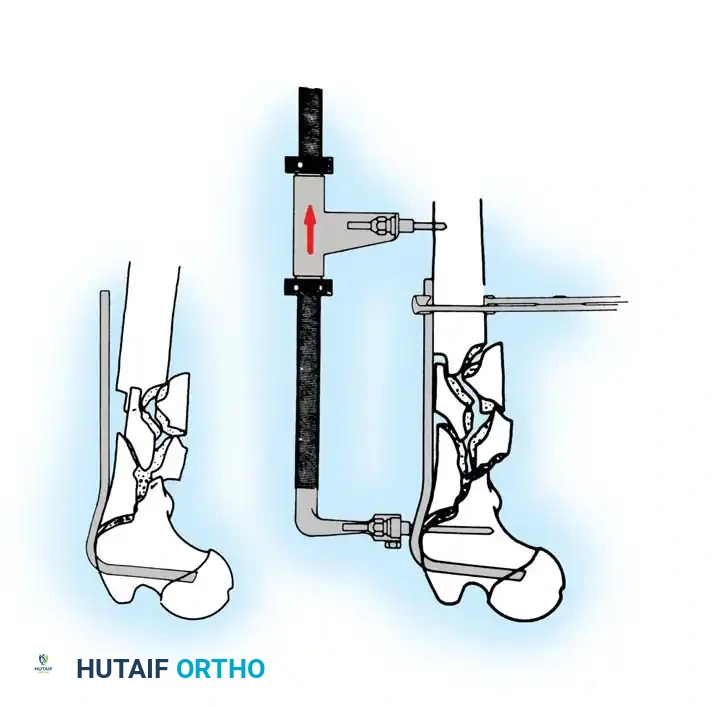

1. Patient Positioning and Reduction

The patient is placed supine on a radiolucent fracture table. The operative leg is secured in a traction boot, and the well leg is placed in a hemilithotomy position or scissored posteriorly to allow unobstructed access for the C-arm fluoroscope.

Proper patient positioning on the fracture table is paramount. Ensure the C-arm can freely rotate from AP to lateral without obstruction.

Closed Reduction Maneuver:

1. Apply longitudinal traction to restore leg length.

2. Internally rotate the leg (typically 10 to 15 degrees) to correct the external rotation deformity and bring the femoral neck parallel to the floor.

3. Verify reduction on both AP and lateral fluoroscopic views. An acceptable reduction must have cortical apposition medially and anteriorly.

5. Intramedullary Nailing (For Unstable Fractures)

If a cephalomedullary nail is chosen, the entry point is established at the tip of the greater trochanter (or slightly medial, depending on the specific implant design).

Insertion of the cephalomedullary nail down the femoral shaft. Care must be taken not to distract the fracture site during insertion.